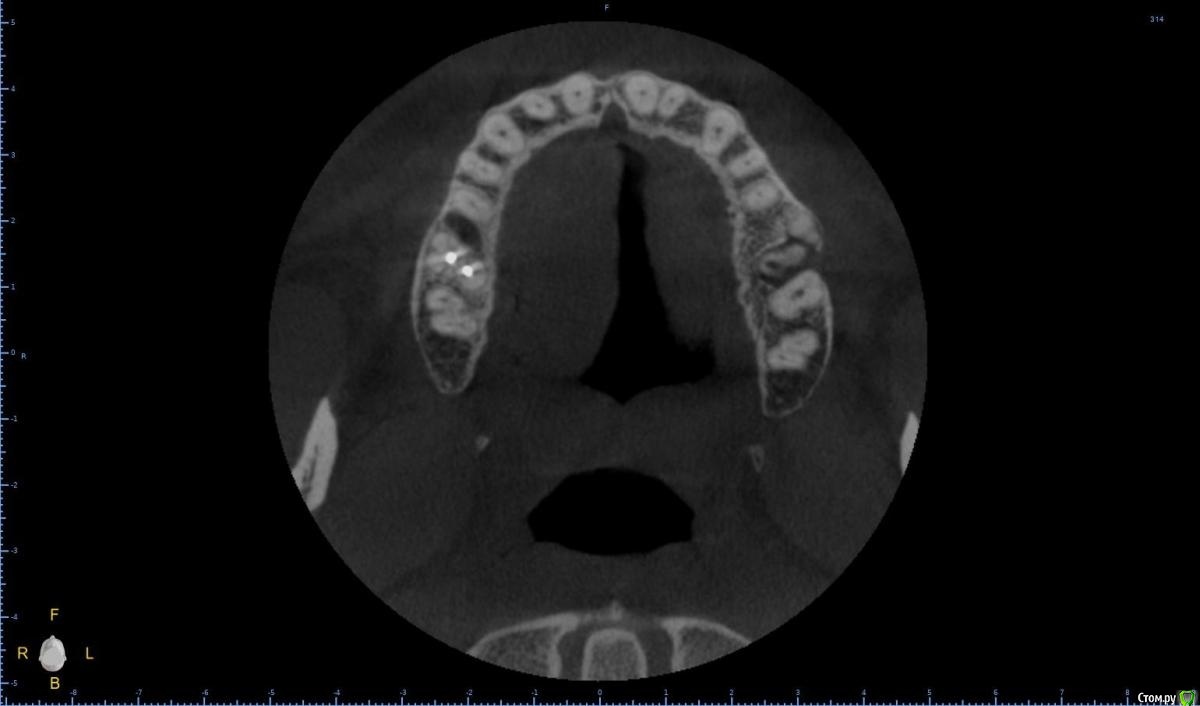

Raystom Опубликовано 20 февраля, 2021 Поделиться Опубликовано 20 февраля, 2021 Обратилась пациентка с неприятными ощущениями в области зубов 26, 27, во рту эти зубы показались мне темнее остальных, на КТ видна вот такая красота. Каков план лечения в таких ситуациях? Попробовать отделить пазуху от грануляций или просто удалить и после лечения ЛОРа идти на закрытие ОАС? Как после восстанавливать кость? И какие временные промежутки. Понимаю, что многие скажут при таких вопросах передать другим, но это не мой вариант. Мб есть литература по подобным случаям? Ссылка на комментарий

Карен Аванесов Опубликовано 22 февраля, 2021 Поделиться Опубликовано 22 февраля, 2021 Обратилась пациентка с неприятными ощущениями в области зубов 26, 27, во рту эти зубы показались мне темнее остальных, на КТ видна вот такая красота. Каков план лечения в таких ситуациях? Попробовать отделить пазуху от грануляций или просто удалить и после лечения ЛОРа идти на закрытие ОАС? Как после восстанавливать кость? И какие временные промежутки. Понимаю, что многие скажут при таких вопросах передать другим, но это не мой вариант. Мб есть литература по подобным случаям?Аккуратно удалить, убрать грануляции, инструментально уточнить есть ли сообщение с пазухой (Думаю что нет), если и есть, коллаген, и лунку ушит. Динамичный контроль. Ссылка на комментарий

колесников Опубликовано 25 февраля, 2021 Поделиться Опубликовано 25 февраля, 2021 Киста сделала синуслифтинг,этот объём надо сохранить,колапол резорбируется быстро и через 3-6 мес останется 3мм,графт не скиснет,а созреет по форме дефекта,надо избежать вторичного инфицирования. Перекрыть вестибулярным лоскутом лунку не получится,раскрытие-инфицирование,боль,отёк,контрактура,смешение биотипа. Зачем? Можно нёбный мобилизовать или выбрать другой способ герметичного закрытия лунки Ссылка на комментарий

Raystom Опубликовано 25 февраля, 2021 Автор Поделиться Опубликовано 25 февраля, 2021 Киста сделала синуслифтинг,этот объём надо сохранить,колапол резорбируется быстро и через 3-6 мес останется 3мм,графт не скиснет,а созреет по форме дефекта,надо избежать вторичного инфицирования. Перекрыть вестибулярным лоскутом лунку не получится,раскрытие-инфицирование,боль,отёк,контрактура,смешение биотипа. Зачем? Можно нёбный мобилизовать или выбрать другой способ герметичного закрытия лункиПонятно, спасибо, буду делать Ссылка на комментарий